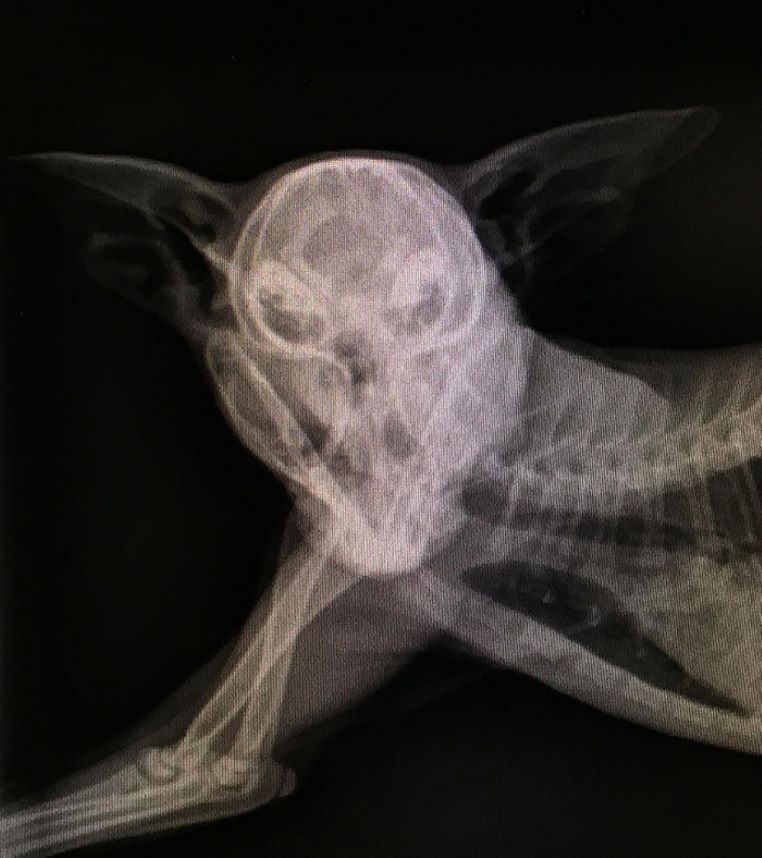

Cette fois-ci, c’est la radiographie d’une chatte enceinte !

galerie-rayon-x-chatte-enceinte